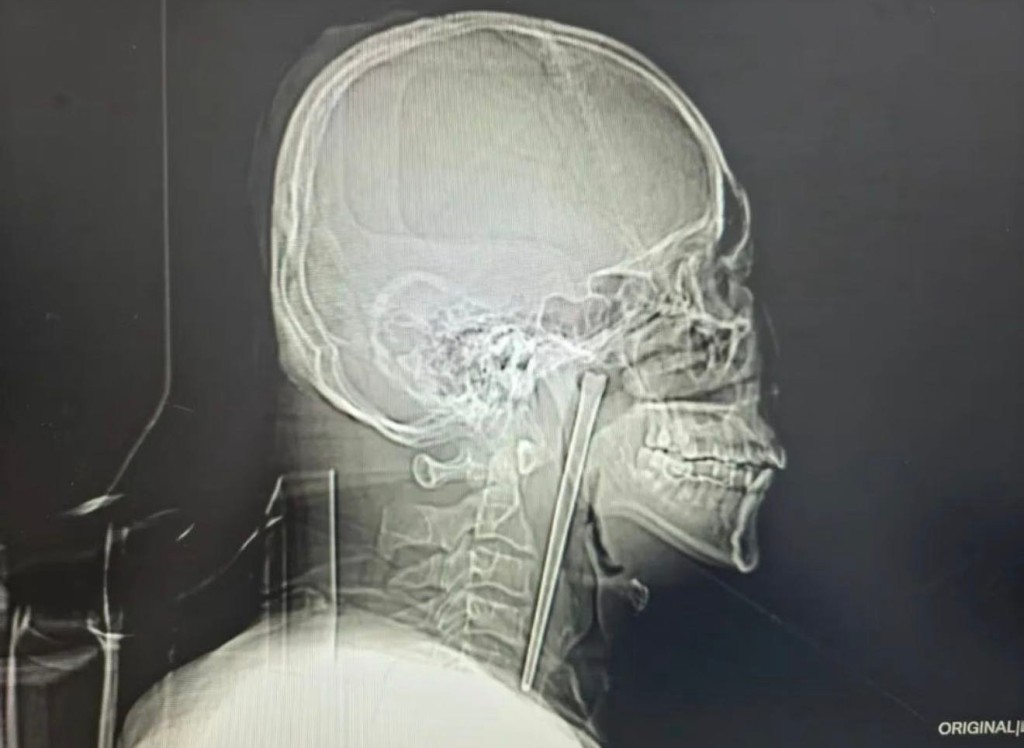

人體竟能藏筷子8年?遼寧大連一名46歲男子,近日因咽喉劇痛及強烈異物感求醫。醫護人員檢查發現,男子咽喉竟有一根長達12厘米的金屬筷子。據男子透露,筷子已跟自己為伴8年,讓人匪夷所思。

網傳男子咽喉留有筷子。《瀟湘晨報》

內地《瀟湘晨報》報道,該名姓王的男子8年前在進食時,意外誤吞一根金屬筷子。當時他雖感不適,但因沒有出現呼吸困難,加上對醫生提出的「切開頸部」取筷手術方案心存恐懼,最終寧願放棄治療。

經檢查,醫生赫然發現一根金屬筷子嵌入其右側咽喉後壁,外露部分約3厘米。幸運的是,筷子並未造成明顯的破潰或出血。考慮到王先生對大型手術的恐懼,醫生成功透過微創手術取出筷子。